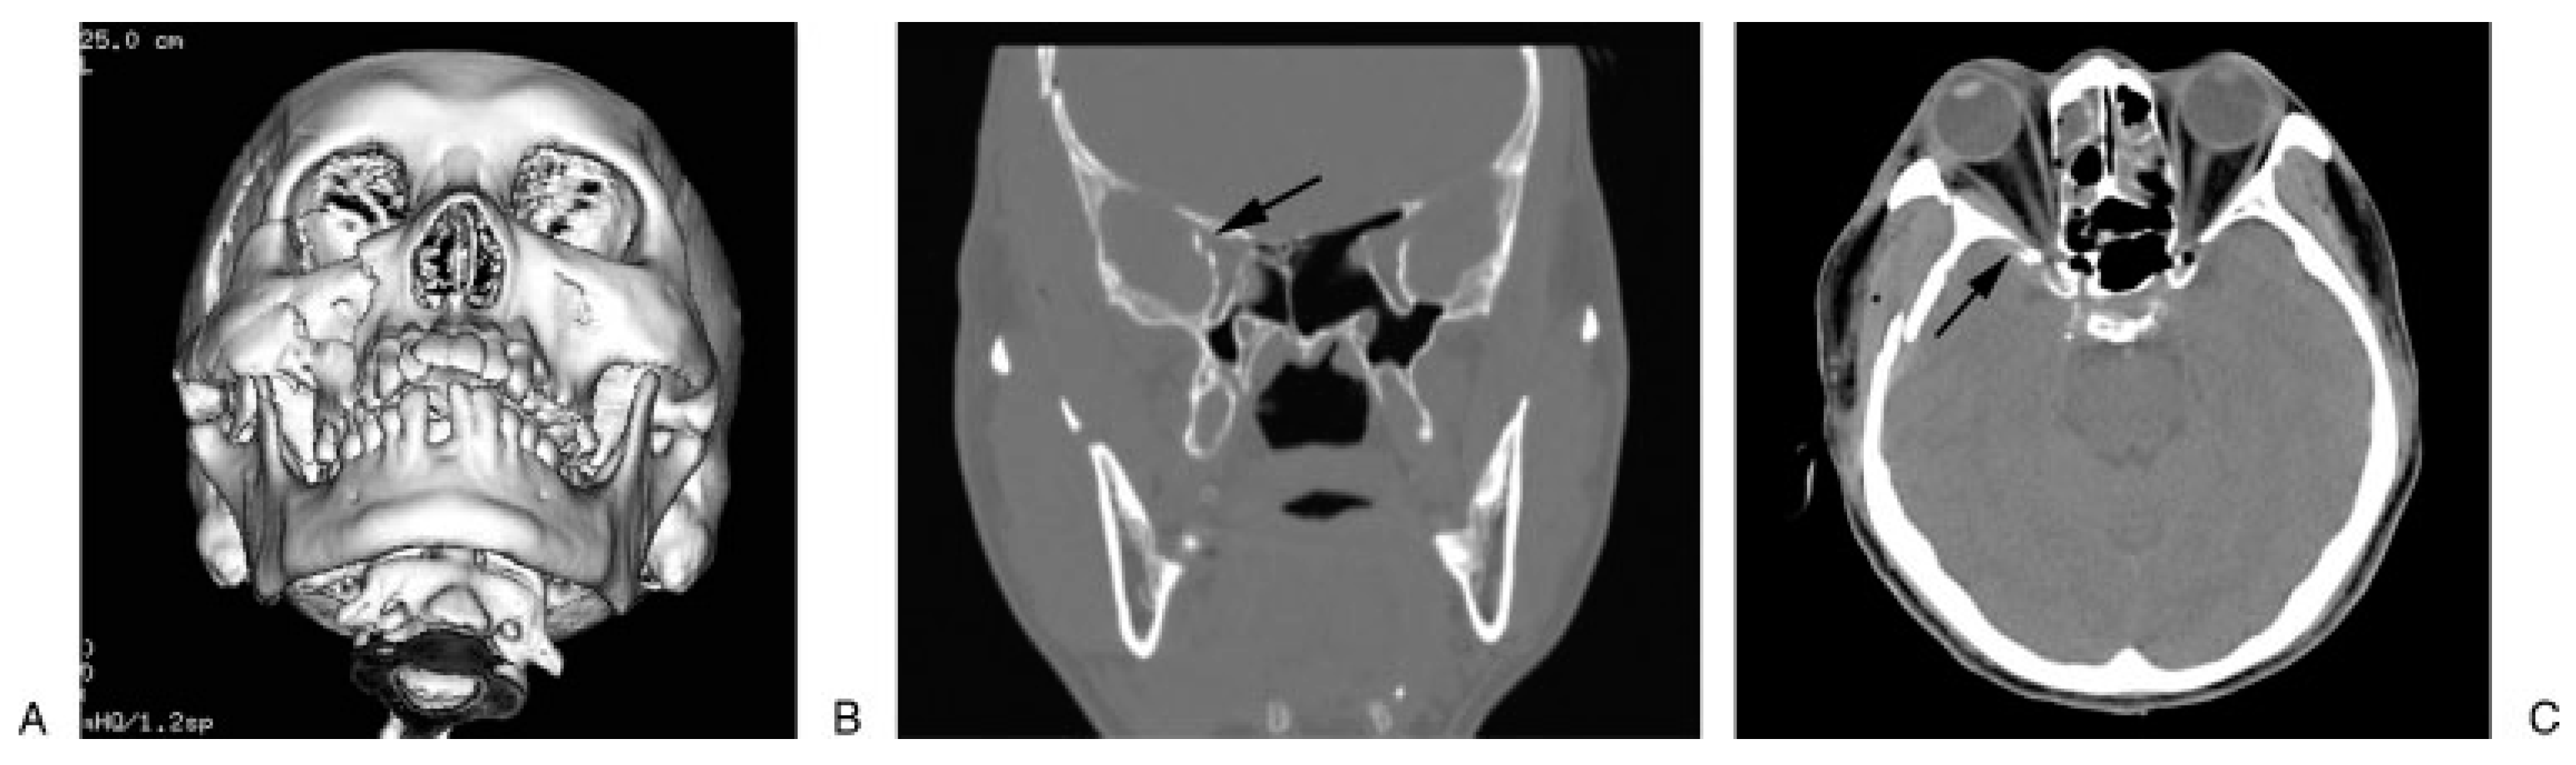

Diagnosis of traumatic SOFS is based on the clinical symptoms, signs mentioned above, and radio- graphic examination. Optimal plain film viewing of the SOF with a posterior/anterior orbital projection can be obtained in a 20–25 degree tilt of the head (Caldwell projection)[23] before CT emerged. However, in severely traumatized patients, plain films are often difficult to obtain and can be hazardous especially when there is a concomitant cervical trauma. Angiography is a useful tool in revealing the traumatic CCSF or carotid aneur- ysm causing SOFS [28,30]. CT scan is an excellent tool for radiologic diagnosis in the traumatized patients. In contrast to plain radiographs, small bony fragments or retroorbital hematoma with compression around SOF can be visualized by fine-cut CT scan (2 mm slices). CT scan demonstrates that fractures in the region of the orbital apex seem to exist more often than thought previously [31]. The new spiral CT equipment is a prom- ising tool to improve the diagnostic accuracy, which can provide a detailed information of SOF in the axial plane, coronal projection, and three-dimensional CT reformatted images (Figure 3). It can help avoid the discomfort of neck hypertension while obtaining the coronal CT slices by the traditional CT machine, and also provide information related to neighboring brain injury and concomitant craniofacial fractures. Nowa- days, the technique of measuring the width of SOF using CT scans is simple and compatible to the real width in cadavers [6].

Figure 3.

Fractures of right temporal, sphenoid, and zygomatic bone are observed on the computed tomographic (CT) scan. The superior orbital fissure (arrow) becomes narrow and compressed by the sphenoid fracture. (A) Submental view on three- dimensional CT (3D-CT). (B) Coronal plane. (C) Horizontal plane.